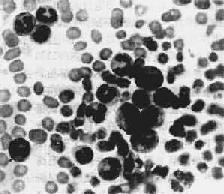

1.周围血像周围血白细胞显著增多,数量正常或减少者少见。CML时白细胞增多尤为明显,多在10万~至80万/μ1之间,少数甚至可超过100万,其中大多数为较成熟的中、晚幼和杆状核粒细胞,早幼粒和原粒细胞很少(图11-7)。嗜碱性和嗜酸性粒细胞也增多。CML时中性粒细胞内碱性磷酸酶常缺如或降低。这点有助于与类白血病反应相区别。CLL血白细胞总数多在3万~10万/μ1之间。血像单一,绝大多数为成熟的小淋巴细胞,只有少数幼淋巴细胞。慢性白血病早期贫血较轻,血小板无明显减少。CML时血小板常增多。晚期有明显贫血和血小板减少。

图11-7 慢性粒细胞性白血病

周围血内白血病细胞主要为中幼粒细胞